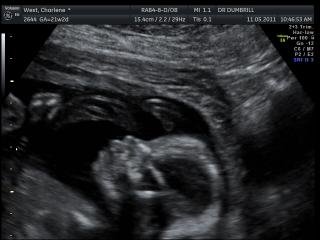

So, I told my husband, Jeremy about my plan of action: an intentional caesarean in hospital. He frowned a little… and said disapprovingly, “Charlene, millions of women have given birth before you – what is wrong with you? You have to try.” To say I was irritated is an understatement… And so, I tried my doctor, Doctor Douglas Dumbrill at Vincent Pallotti Hospital, surely he would listen? He said the same, only a bit different; “Charlene, if you want a caesarean, then you need to go to that hospital over there (motioning with his hands in a southerly direction). I will not just give you a caesarean without a medical reason.” He added that I should go home, think about it, do more research on the topic and come back with questions.